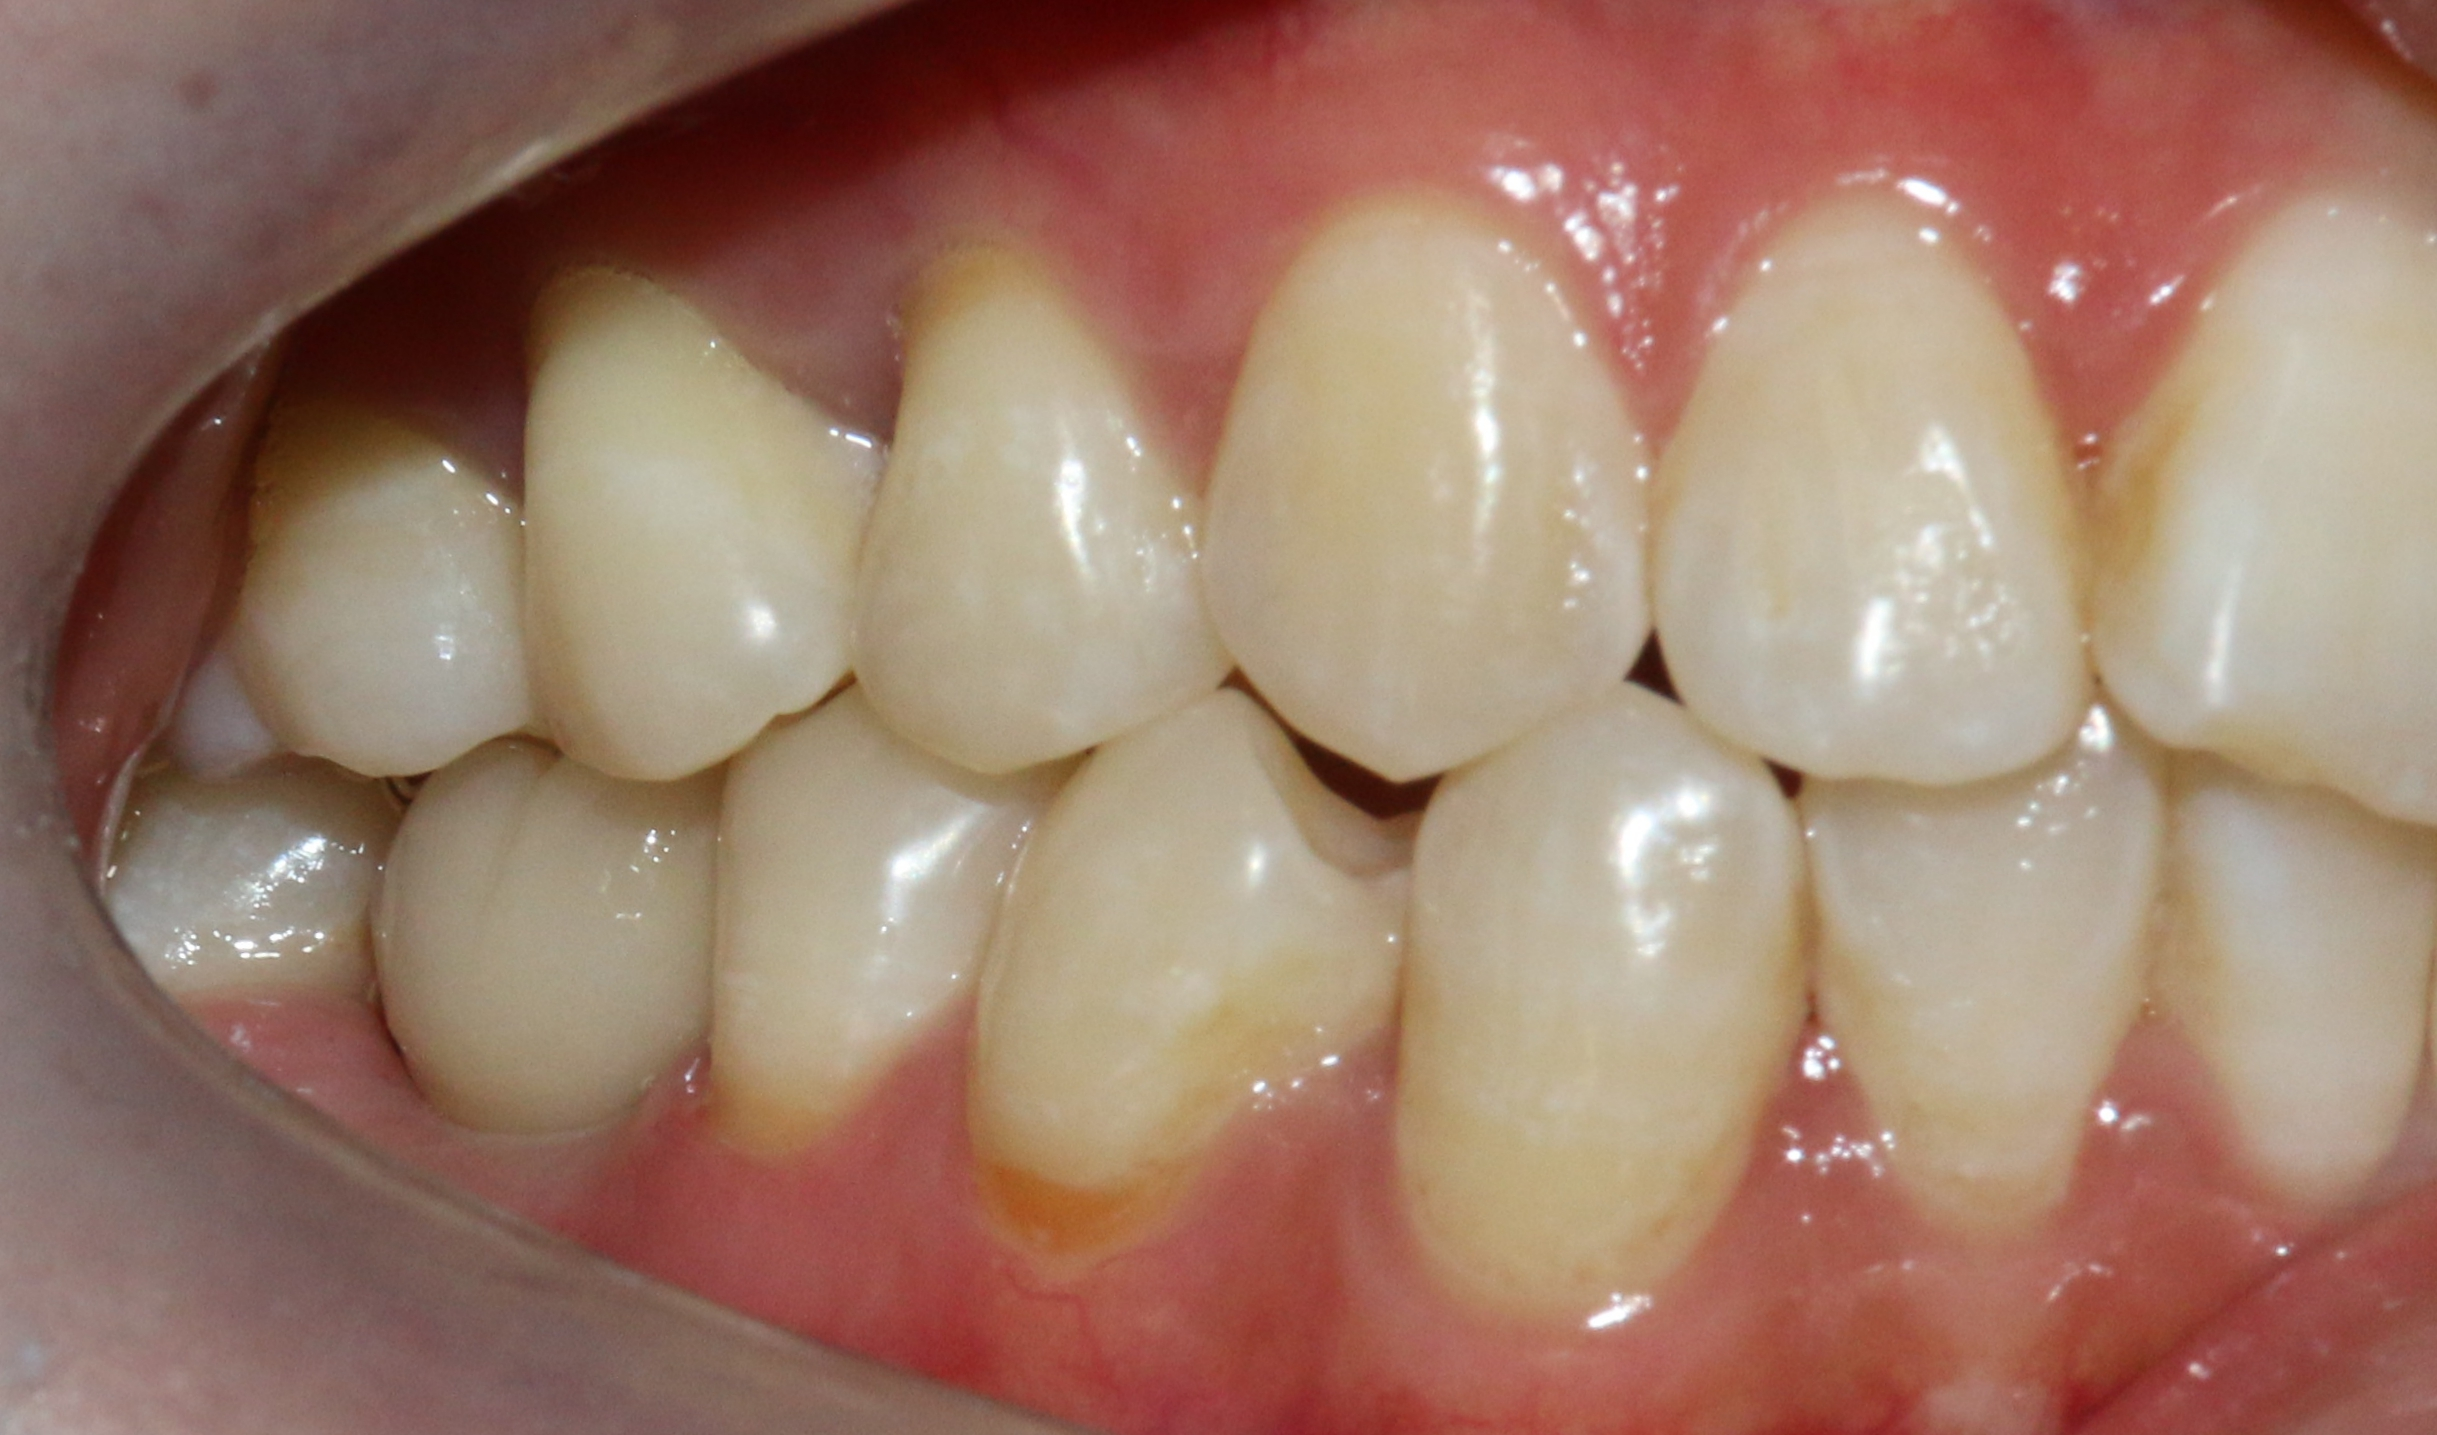

患者:苗** 女 27

初诊时间:2016年9月4日

现病史:8个月前,患者右下后牙因龋坏无法治疗在我院拔除,现影响进食,就诊。